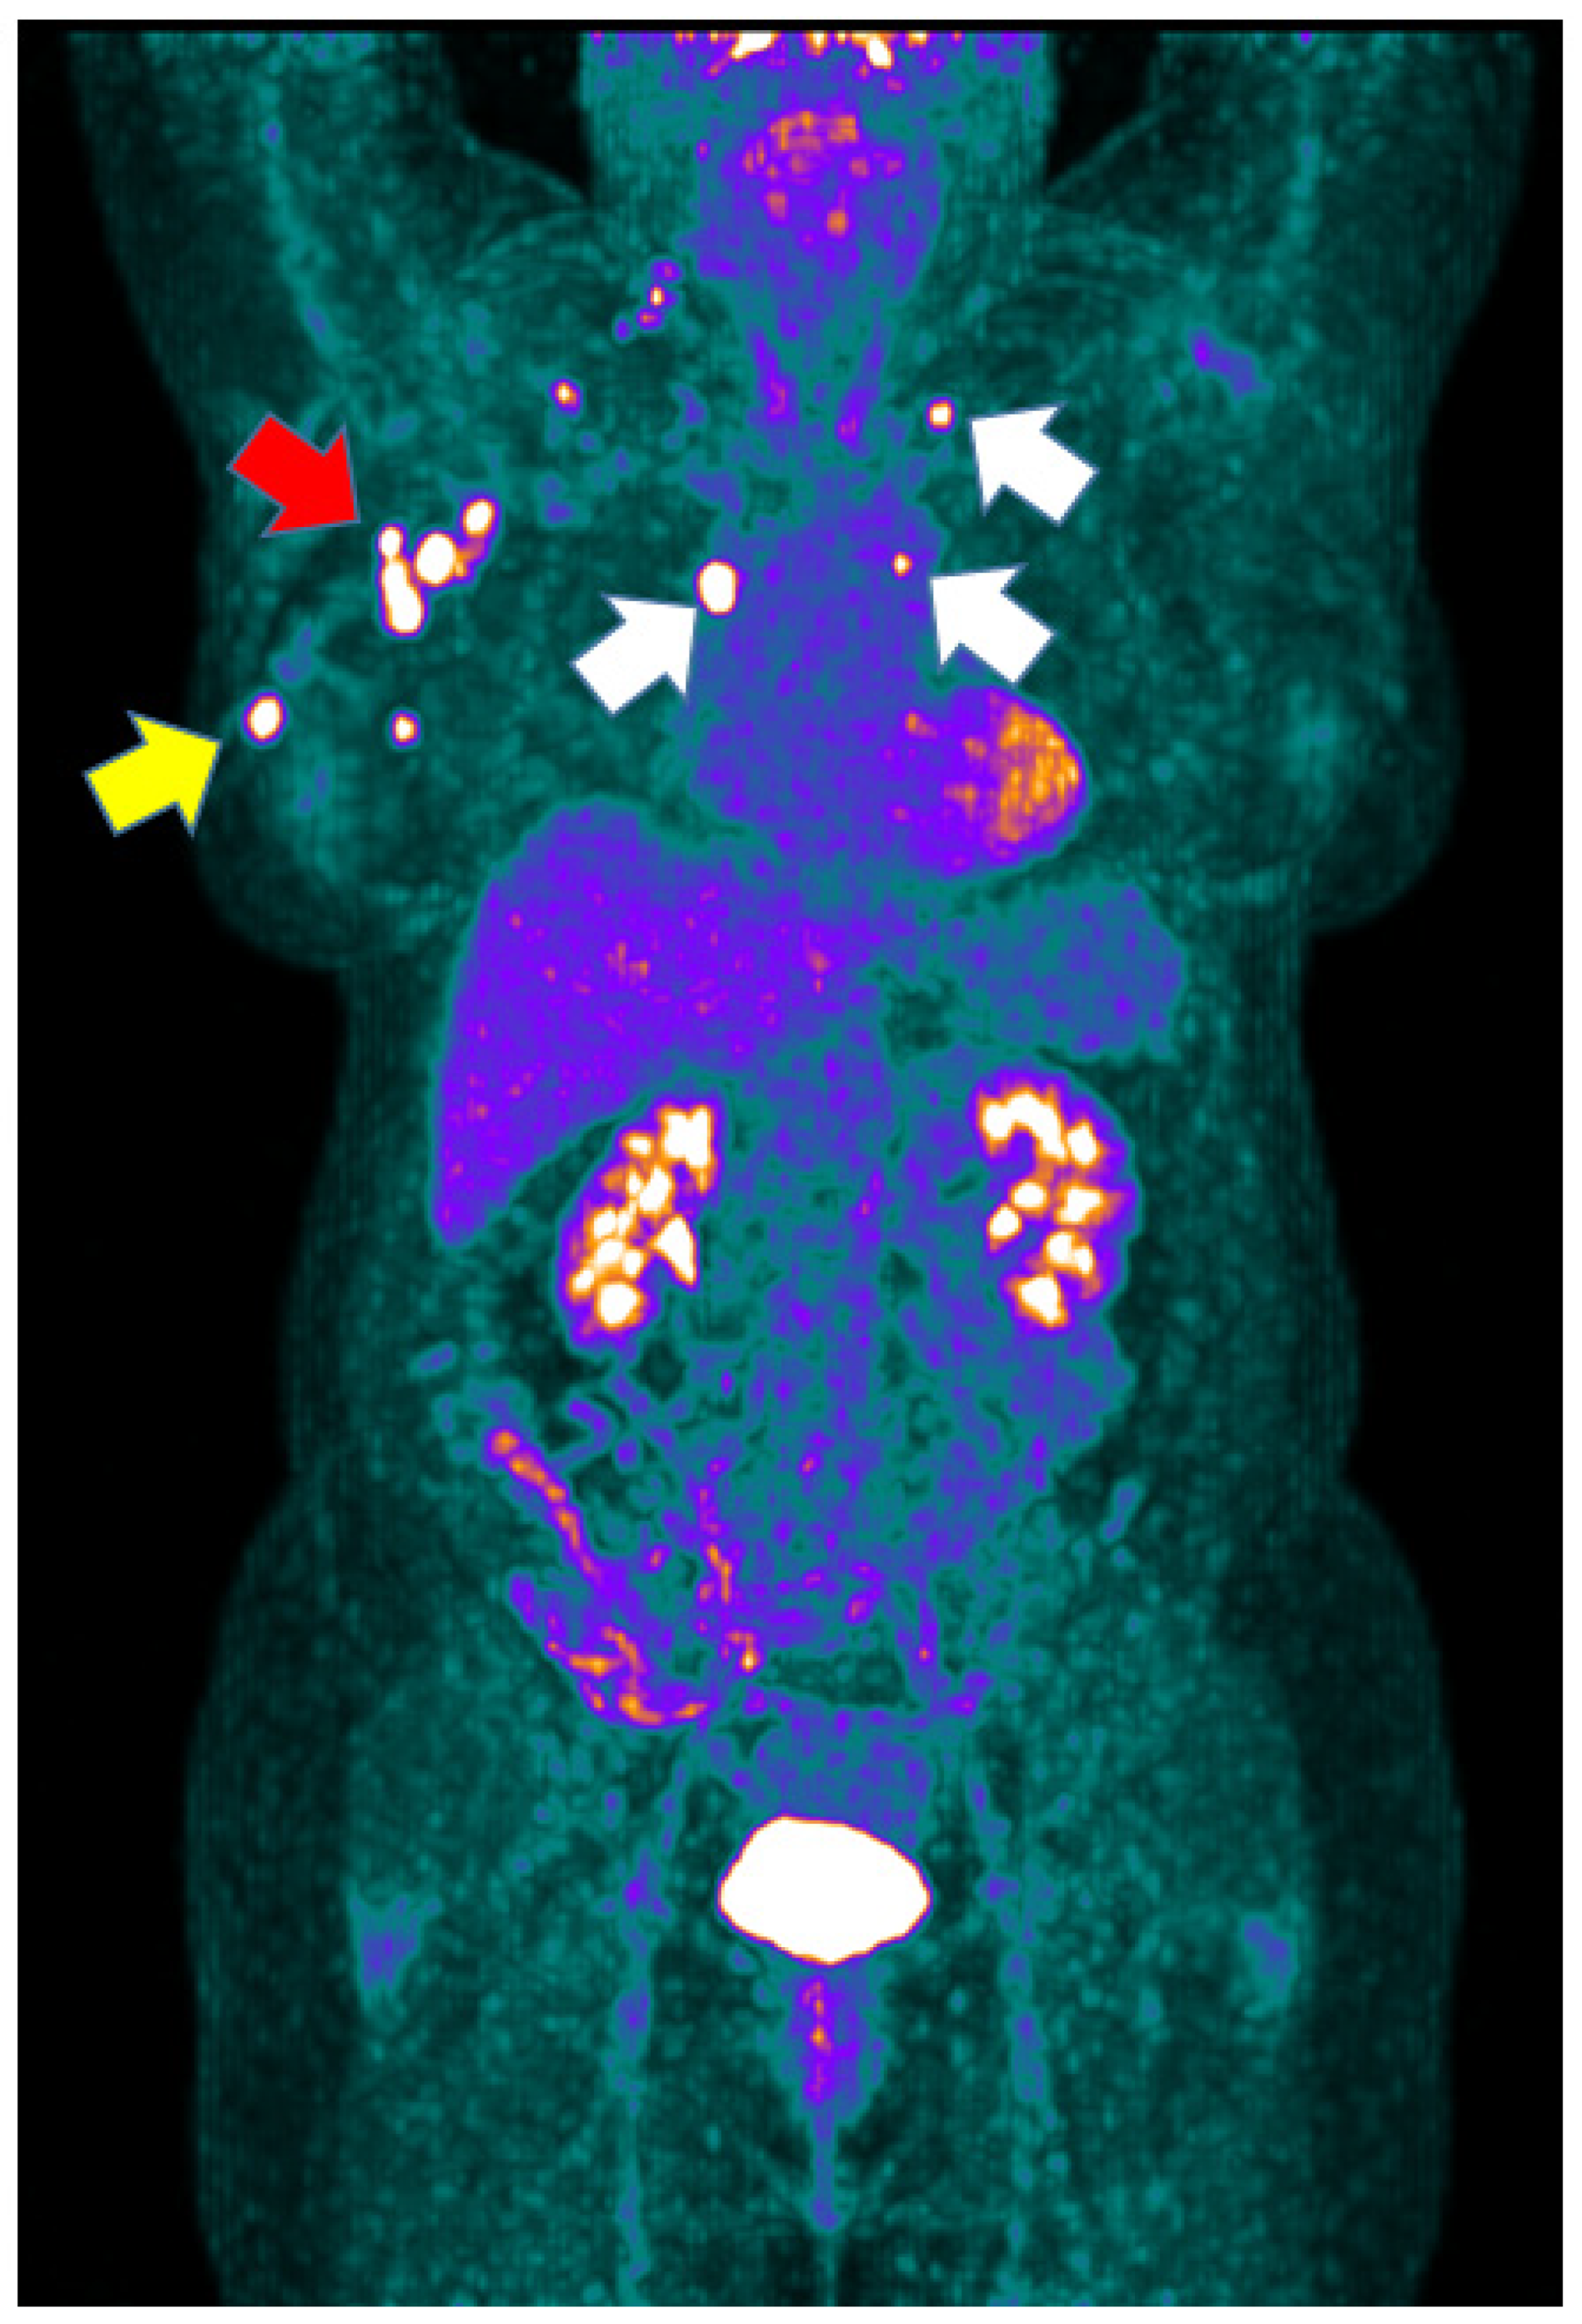

3.1. [18F]FDG PET/CT Results

| Breast PET No Yes | 0 49 (100%) | 1 (3%) 32 (97%) | 1 (3.1%) 31 (96.9%) | 0.464 |

| Axillary LN PET No Yes | 17 (34.7%) 32 (65.3%) | 18 (54.5%) 15 (45.5%) | 15 (46.9%) 17 (53.1%) | 0.190 |

| Distant LN PET No Yes | 36 (75.3%) 13 (26.5%) | 26 (78.8%) 7 (21.2%) | 26 (81.3%) 6 (18.8%) | 0.693 |